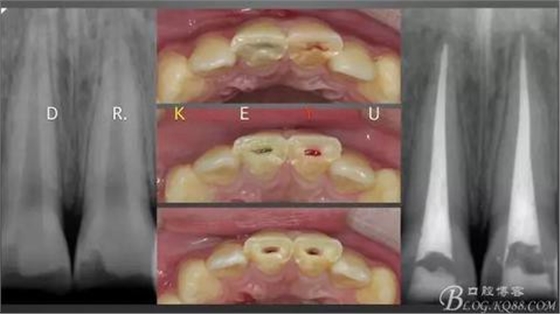

CASE 3—16歲少年外傷后一周來診,RCT后纖維樁及樹脂功能恢復(fù)

一個(gè)牙髓壞死,一個(gè)活髓,首先一次性根管治療

取研究模型,制作蠟型

復(fù)診于導(dǎo)板下纖維樁及樹脂功能恢復(fù)